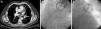

En el estudio TC de tórax se identificó una lesión con aspecto de «manguito» de partes blandas con distribución peribroncovascular en el lóbulo superior izquierdo que fue interpretada inicialmente como posible tumor (fig. 1A, flecha). A pesar de que existía la sospecha clínica de estenosis de la vena pulmonar como causa de la hemoptisis, ante el hallazgo radiológico se decidió realizar broncoscopia con endoscopio flexible para toma de biopsia a fin de descartar tumor a dicho nivel, donde se objetivó una mucosa con petequias y fácil sangrado al paso del broncoscopio. Durante el procedimiento, el paciente presentó un importante sangrado desde el bronquio principal izquierdo, que requirió intubación orotraqueal selectiva del bronquio principal derecho y traslado a la unidad de cuidados intensivos.

Se realizó angiografía pulmonar, que mostró estenosis de la vena pulmonar superior izquierda (fig. 1B, en la que se objetiva disminución del calibre vascular a nivel de dicha vena). Se procedió a angioplastia con balón a este nivel, consiguiéndose repermeabilización, con buen resultado angiográfico posterior (fig. 1C). Tras estabilización del paciente y posterior alta, ingresó de forma programada a los 2meses para la realización de angioplastia con colocación de stent.

La hemoptisis ha sido descrita en la literatura científica como una rara forma de presentación de estenosis de venas pulmonares2, sin que se haya aclarado la etiopatogenia de la hemoptisis en estos pacientes. Aguilar-Cabello et al.3 describen un caso similar en el que el examen anatomopatológico de una muestra de lobectomía mostró un tejido pulmonar congestivo. El aumento de presión venosa en la zona preestenótica justificaría la congestión del tejido pulmonar y el riesgo de sangrado a nivel de la mucosa en dicha zona. En nuestro paciente, la imagen observada en la TC de tórax al inicio (fig. 1A) parece corresponder a edema y fibrosis peribroncovascular secundaria a congestión por trombosis de la vena. Este hallazgo radiológico puede ayudar a comprender un poco más la fisiopatología y servir como referencia para ayudar a otros clínicos a apoyar el diagnóstico de esta entidad.